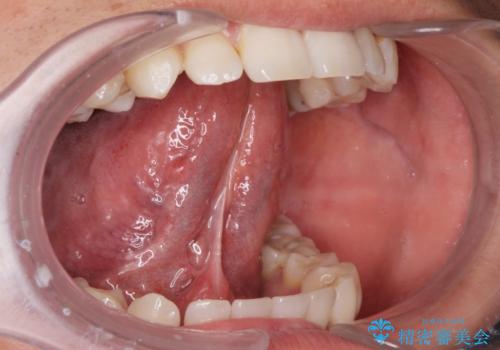

- ラ行が言いにくい。舌が動かしにくいとの事で来院。

舌小帯の形成術を行い、舌の可動域を広げました。

舌の可動範囲が広がり、ラ行が言いやすくなりました。

舌小帯切除術は当日行うことが可能です。